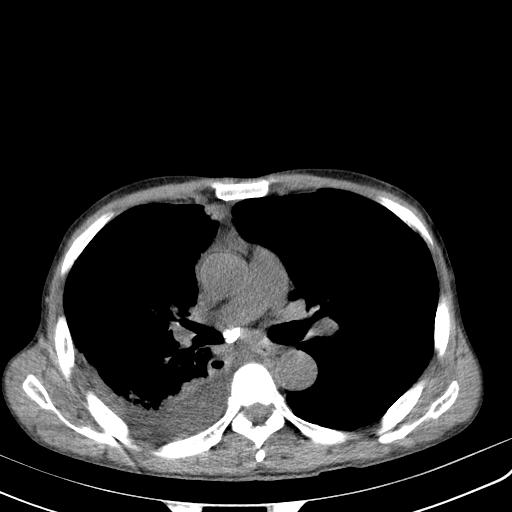

男性 75  咳嗽 一周前发热最高达39

右肺继发型tb并右侧tb性胸腔炎,右侧胸腔大量积液并右下肺膨胀不全,慢支肺气肿、多发肺大泡。建议抽胸水实验室检查并复查排除恶性在占位。

右上肺继发型肺结核,右胸腔中等量积液。

左上肺大泡。

结核的基础上有纵隔淋巴结肿大,右侧有胸水,但右侧纵隔反而窄,说明有肺有不张。

再就是右下肺有块影,和不张混合,还是不能除外肺癌。

补充材料,患者2月份ct片大致正常,双侧胸腔积液,2月份抽胸水未发现ca细胞,现患者发热,痰多,各气管通畅,

1)右肺继发型肺结核。2)左肺胸膜下多发性肺大泡。3)右侧胸腔积液。